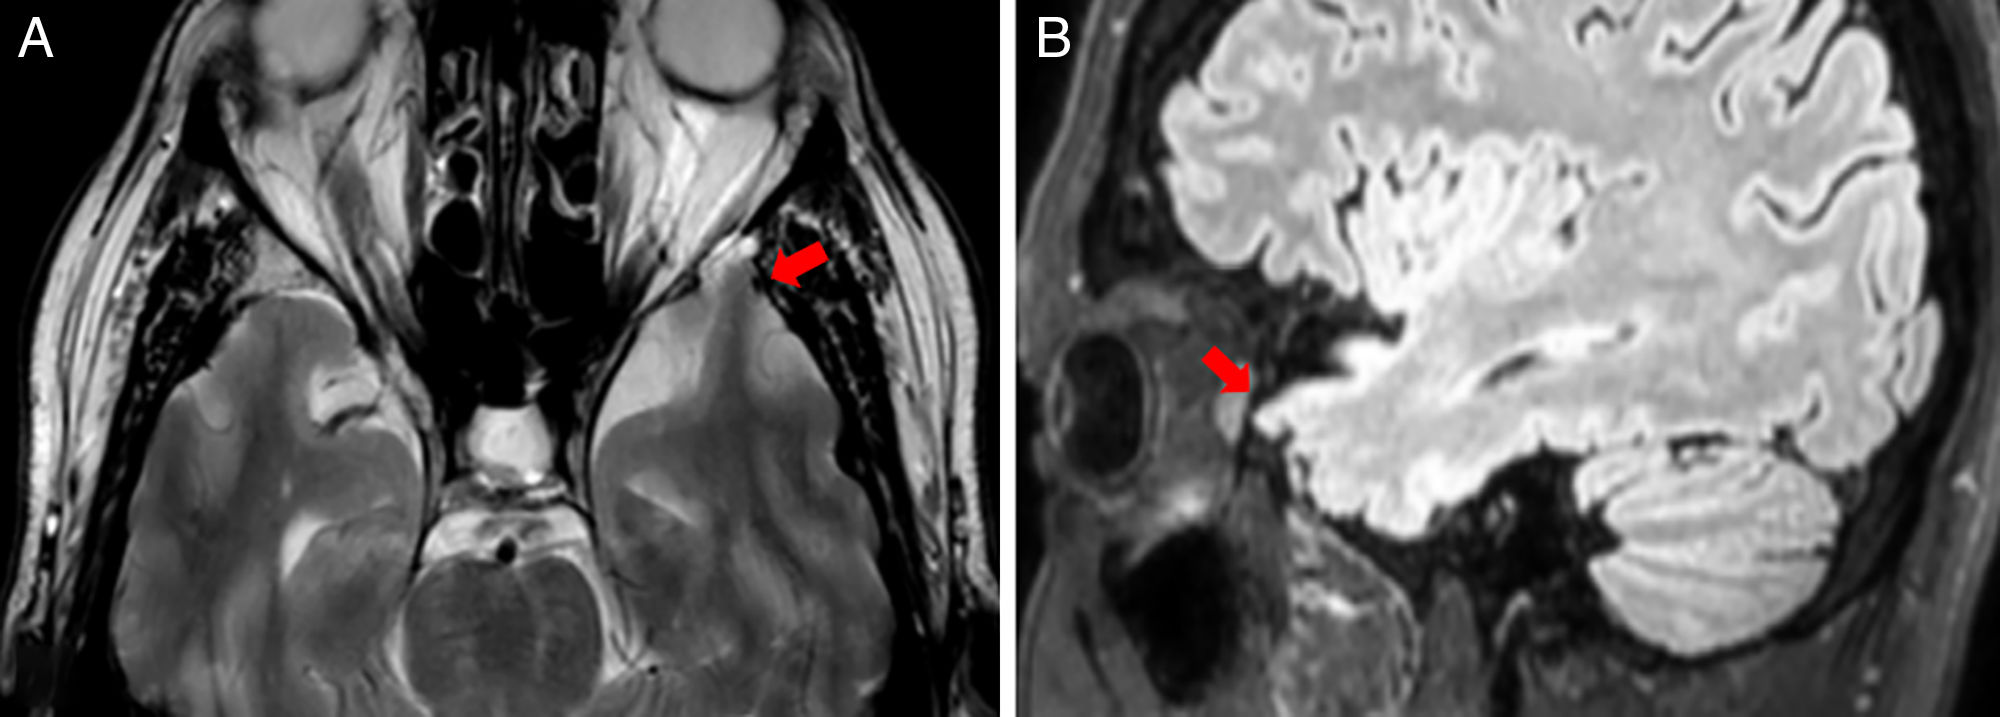

MSA

hot cross bun sign

hyperintensities of cerebellar peduncles